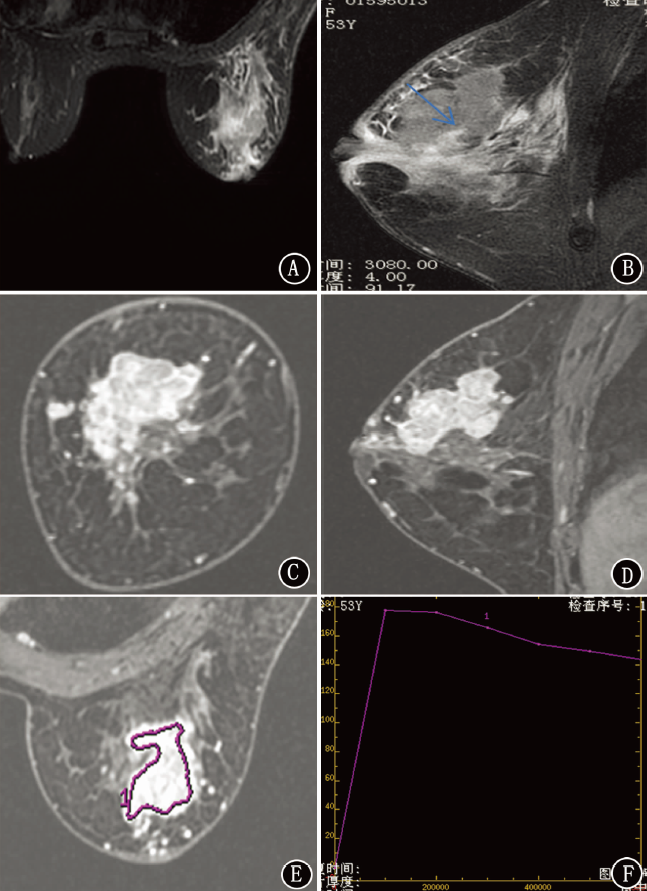

目的 探讨MRI对乳腺成簇环样强化良恶性病变的诊断价值。方法 回顾性分析2017年10月至2019年7月在空军军医大学唐都医院因临床触诊、超声或X线检查可疑恶性病变而行MRI检查表现为成簇环样强化的68例乳腺疾病患者的影像征象。采用χ2检验或Mann-Whitney U检验比较良性病变和恶性病变间分布方式、T2抑脂信号强度、时间-信号强度曲线(TIC)、有无导管扩张、有无周围腺体水肿、有无胸大肌水肿的差异,采用二项logistic回归模型分析乳腺恶性病变MRI影像征象的相关危险因素。结果 68例患者共68处成簇环样强化病变,均为单发病变,其中良性18例(26.5%),以浆细胞性乳腺炎最多见(9例);恶性50例(73.5%),以浸润性乳腺癌最多见(40例)。浆细胞性乳腺炎影像学特征多表现为成簇环样强化,分布方式呈区域样分布,T2抑脂稍高信号,TIC为Ⅲ型,有导管扩张,有周围腺体及胸大肌水肿;浸润性乳腺癌影像学特征多表现为成簇环样强化,分布方式呈区域样分布,T2抑脂等信号,TIC为Ⅲ型,无导管扩张,有周围腺体及胸大肌水肿。在MRI征象T2抑脂信号强度及导管扩张,良性病变和恶性病变间差异均具有统计学意义(Z=3.003,P=0.003;χ2=7.174,P=0.007);而在分布方式(χ2=5.510,P=0.313)、TIC类型(χ2=3.538,P=0.133)、周围腺体水肿(χ2=0.164,P=0.686)及胸大肌水肿(χ2<0.001,P>0.999),差异均无统计学意义。二项logistic回归模型分析显示,T2抑脂信号强度呈等信号(OR=0.182,95%CI为0.036~0.914,P=0.039)、病变无导管扩张(OR=0.198,95%CI为0.047~0.846,P=0.029)是乳腺恶性病变的相关危险因素。结论 乳腺癌MRI检查表现为成簇环样强化的影像征象,T2抑脂信号强度呈等信号、病变无导管扩张是乳腺恶性病变的相关危险因素,MRI有助于乳腺病变的早期发现、早期诊断。

Objective To investigate the diagnostic value of MRI in benign and malignant breast lesions with cluster ring enhancement. Methods The imaging signs of 68 patients with clustered ring enhancement who underwent MRI examination due to clinical palpation, ultrasound or X-ray examination for suspected malignant lesions in Tangdu Hospital of Air Force Military Medical University from October 2017 to July 2019 were retrospectively analyzed. The differences between benign and malignant lesions in the distribution pattern, T2 lipid suppression signal intensity, time-signal intensity curve (TIC), ductal dilatation, peripheral gland edema, pectoralis major edema were compared using χ 2 test or Mann-Whitney U test, and the risk factors of MRI imaging signs of malignant breast lesions were analyzed using binomial logistic regression model. Results There were 68 cluster ring enhancement lesions in 68 patients, all of which were single lesions, among which 18 cases (26.5%) were benign, and the common lesions were plasma cell mastitis (9 cases). Fifty cases (73.5%) were malignant, and the most common type was invasive breast cancer (40 cases). Imaging features of plasma cell mastitis showed cluster ring enhancement, regional distribution, slightly high signal on fat suppression T2 image, type Ⅲ TIC, with ductal dilatation, edema of peripheral glands and pectoralis major. Imaging features of invasive breast cancer showed cluster ring enhancement, regional distribution, iso-signal on fat suppression T2 image, type Ⅲ TIC, no ductal dilatation, and edema of peripheral gland and pectoralis major. There were statistically significant differences in the intensity of fat-suppression T2 signal (Z=3.003, P=0.003) and duct dilatation (χ 2=7.174, P=0.007) between benign and malignant lesions. There were no significant differences in distribution (χ 2=5.510, P=0.313), TIC type (χ 2=3.538, P=0.133), peripheral gland edema (χ 2=0.164, P=0.686) and pectoralis major edema (χ 2<0.001, P>0.999). The analysis of binomial logistic regression model showed that fat-suppression T2 iso-signal (OR=0.182, 95%CI: 0.036-0.914, P=0.039) and no ductal dilatation (OR=0.198, 95%CI: 0.047-0.846, P=0.029) were the risk factors for breast malignant lesions. Conclusion Breast cancer MRI findings of cluster ring enhancement, fat-suppression T2 iso-signal and no ductal dilatation are related risk factors for malignant breast lesions. MRI is helpful for early detection and diagnosis of breast lesions.